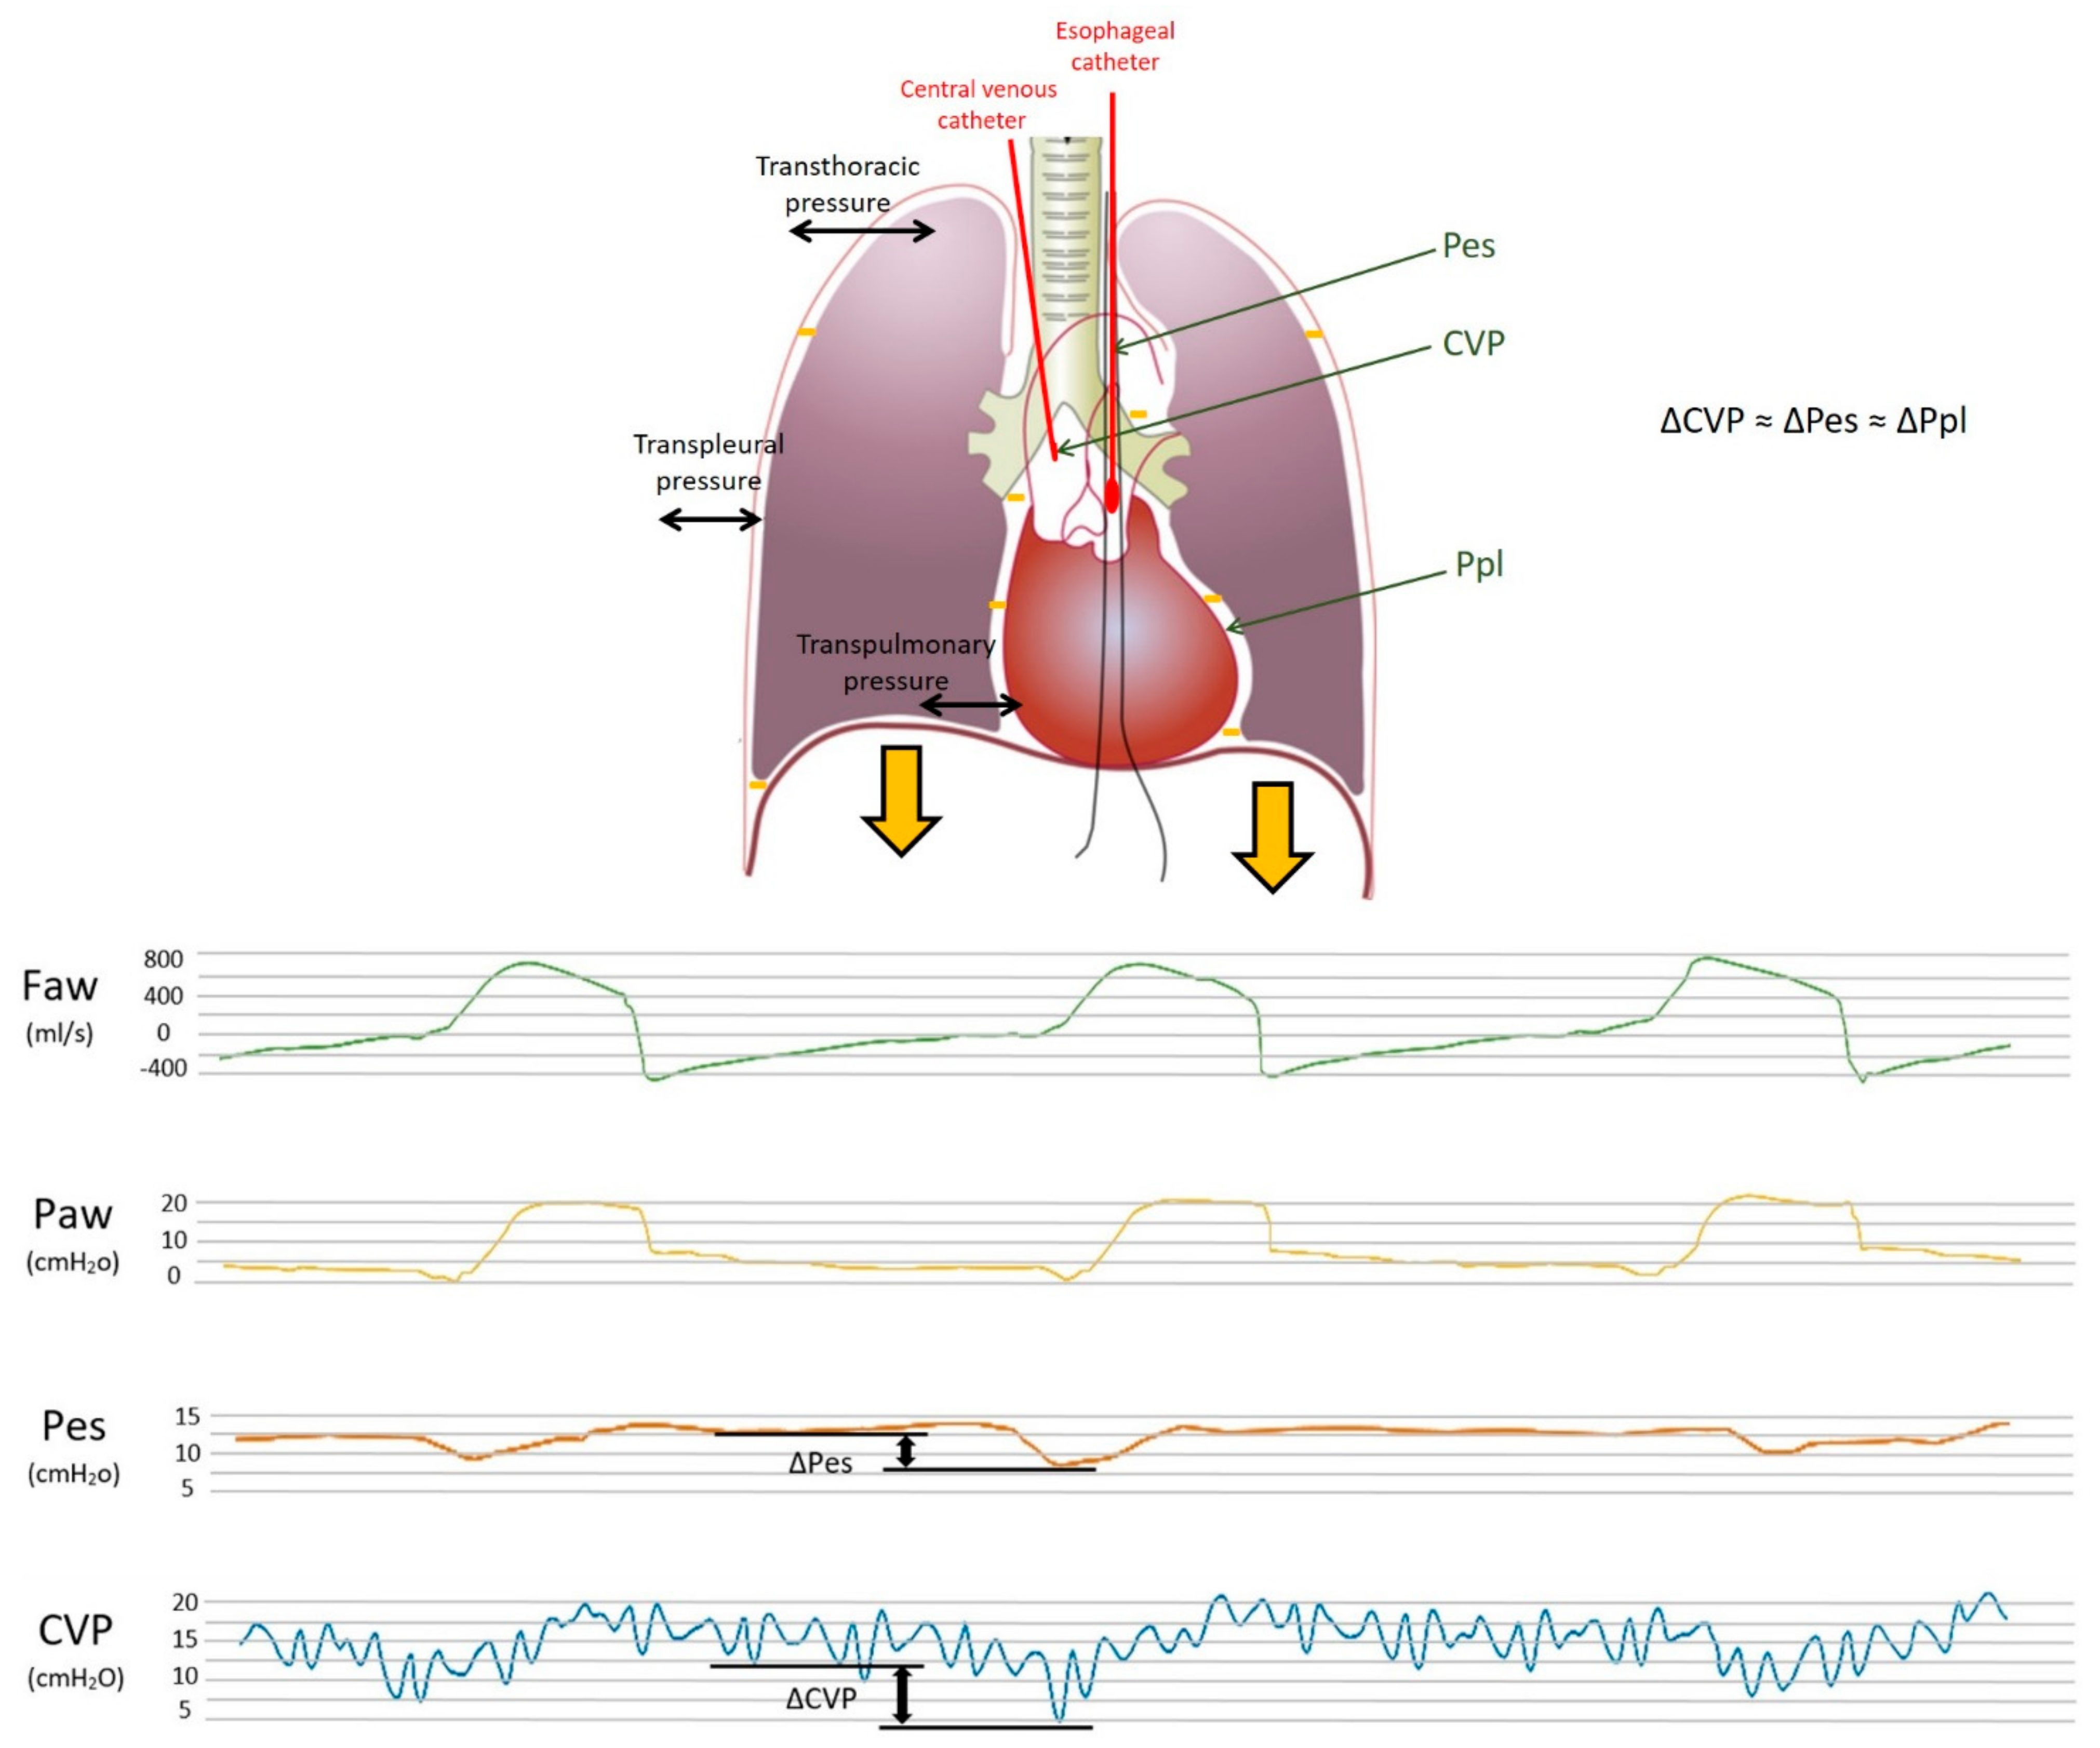

- Kyogoku, M.; Takeuchi, M.; Inata, Y.; Okuda, N.; Shimizu, Y.; Hatachi, T.; Moon, K.; Tachibana, K. A novel method for transpulmonary pressure estimation using fluctuation of central venous pressure. J. Clin. Monit. Comput. 2020, 34, 725–731. [Google Scholar] [CrossRef]

- Colombo, J.; Spinelli, E.; Grasselli, G.; Pesenti, A.M.; Protti, A. Detection of strong inspiratory efforts from the analysis of central venous pressure swings: A preliminary clinical study. Minerva Anestesiol. 2020, 86, 1296–1304. [Google Scholar] [CrossRef]

- Lassola, S.; Miori, S.; Sanna, A.; Cucino, A.; Magnoni, S.; Umbrello, M. Central venous pressure swing outperforms diaphragm ultrasound as a measure of inspiratory effort during pressure support ventilation in COVID-19 patients. J. Clin. Monit. Comput. 2021, 36, 461–471. [Google Scholar] [CrossRef]